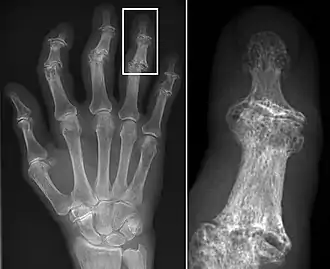

Osteoarthritis

Osteoarthritis (OA) is a degenerative joint disease that affects the junctions of articulating elements, or synovial joints (e.g. knee, shoulder) and is characterized by the damage of cartilage. OA is the most commonly documented pathology found in archaeological human remains and has been used extensively as an activity marker that reflects stress-related activity patterns or occupation.[11] Factors such as age, sex, body size and others also affect its expression.[12]